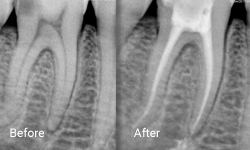

Root canal treatment, also known as endodontic treatment, is performed to save a tooth that has become inflamed or infected due to deep decay, repeated dental procedures, or trauma. During this procedure, the inflamed or infected pulp is carefully removed, and the inside of the tooth is meticulously cleaned and disinfected.

After cleaning, the tooth is filled and sealed with a rubber-like material called gutta-percha. Finally, the tooth is restored with a crown or filling to ensure long-term protection and functionality. This treatment not only alleviates pain but also preserves the natural tooth structure.